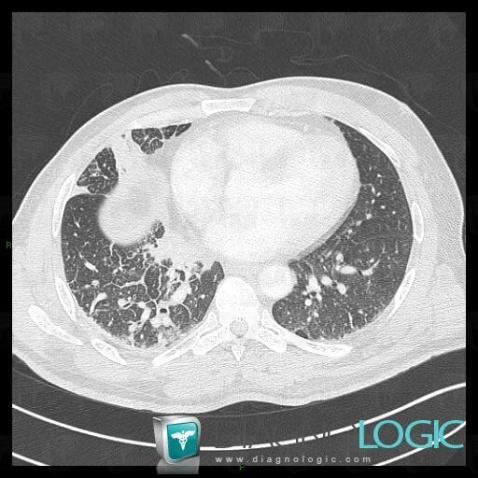

Lymphangite carcinomateuse, Parenchyme pulmonaire, Scanner

Voici les informations spécifiques à l'image clé ci dessus:

- Diagnostic Lymphangite carcinomateuse, Localisation(s) Parenchyme pulmonaire, comportant les gammes Epaississement péri broncho vasculaire / Epaississement septal, Epaississement péri broncho vasculaire / Epaississement septal irrégulier